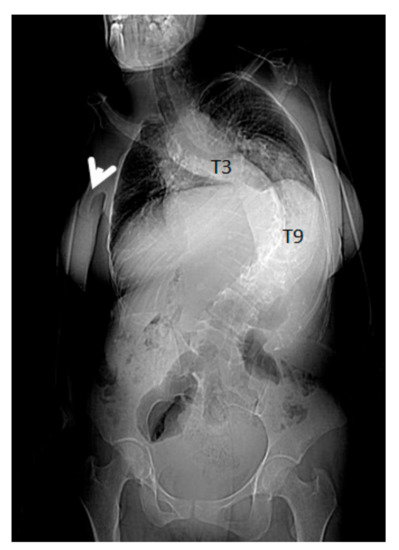

- 3D reconstruction CT scan in a-20-years-old-girl showed severe flattening, fusion, shrinkage and compression of the vanished thoracic spine T3-T9 causing effectively the development of painful kyphoscoliosis. Vanishing bone extended to involve the right shoulder joint resulted in total drop of the right upper limb (Figure 3).